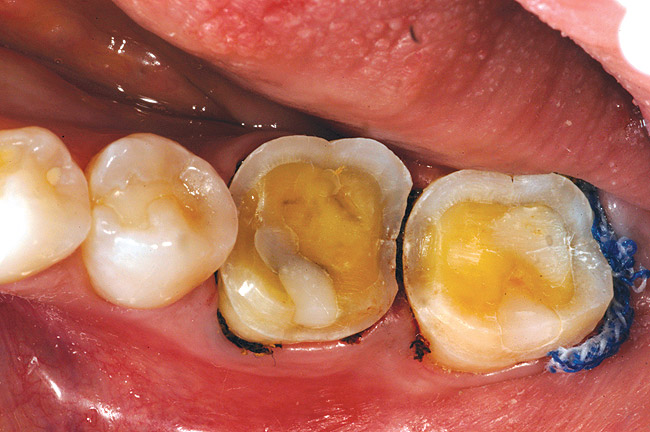

In an isolated field, the temporary restorations are removed and the preparations thoroughly cleaned using a low-pressure, particle-abrasion cleansing protocol (Figure 9A and Figure 9B).40 The restorations are carefully tried on the prepared teeth one at a time. Proximal contacts are adjusted as needed so that each restoration seats fully to place. Accurate fit and marginal integrity are confirmed. Adjoining restorations are tried in en masse to confirm appropriate proximal contacts. Once the accuracy of the restorations themselves and the proximal contacts have been confirmed, the restorations are filled with a translucent try-in paste to provide an accurate esthetic preview of the final result. The occlusion is not evaluated until after the restorations have been luted to the preparations.

If the teeth have not been already isolated and cleaned, rubber dam isolation and air-abrasion micromechanical debridement are completed at this time. Hemostasis must be confirmed and areas of concern addressed. Achieving a clean, dry field in which to cement all-porcelain, adhesively retained restorations is essential to prevent insufficient bond strengths and microleakage.33 The teeth, one at a time, anterior to posterior, are wedged to slightly separate the contact points and thus alleviate any resistance to full seating of the restorations at the cementation phase (Figure 9C). If need be, the occluso-cervical dimension of the wedges should be trimmed to prevent any potential interference to full seating of the restorations.

Figure 9c  The area is isolated and wooden wedges are used to separate the contacts.

Figure 9c